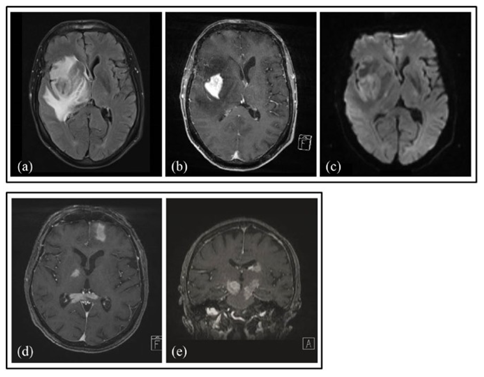

PCNSL患者最常见的临床表现为非特异性神经认知缺陷,很少发生局灶性神经系统症状和体征。大多数免疫功能正常的PCNSL患者存在单个脑肿块,20-40%的免疫功能正常的患者仅报告了多个脑肿块,在幕上和脑室周围位置多见,如图1。头CT扫描发现病变为等密度,而磁共振成像(MRI)对PCNSL的诊断最为敏感,非增强性病变很少见,而病灶周围血管源性水肿很常见。T2加权MRI的低信号和扩散加权成像(DWI)上的扩散受限是PCNSL的典型特征。这些影像学特征可能有助于区分PCNSL和其他疾病,如感染,肿瘤性脱髓鞘病变或胶质瘤。对皮质类固醇的放射学反应很常见,但这并不能确保PCNSL的诊断,因为炎症或脱髓鞘病症也表现如此,在极少数情况下,PCNSL可能存在颅神经或神经根或局灶性脑膜增强的微小局灶性异常。

图1 两名患有原发性中枢神经系统淋巴瘤(PCNSL)的患者(a-c,d和e)的脑磁共振成像(MRI):( a)轴向液体衰减反转恢复(FLAIR)序列,显示由高信号水肿包围的低信号病变; (b)轴向,T1加权,对比度增强序列,具有强烈的均匀对比度增强; (c)扩散加权轴向序列,显示病变中的明亮信号,表明扩散受限。(d,e)轴向和冠状T1加权,对比增强序列揭示多焦点对比增强的PCNSL病变。